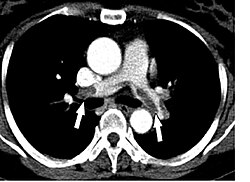

![]() KT vasitəsilə görünən ağciyər tromboemboliyası | |

Kompüter tomoqrafiyası

ATE-ni təsdiq və ya inkar etmək üçün kompüter tomoqrafik pulmonar angioqrafiya (KTPA) aparılması tövsiyə olunur. Bu üsul tromboemboliyaların müəyyən edilməsində tarixi qızıl standart hesab edilir. İnvaziv prosedurdur, yüksək şüalıdır (effektiv şüa dozası 10-20 mSv). Əgər KTPA əks göstərişdirsə (kontrast maddəyə allergiya, hamiləlik, böyrək patologiyaları və s.) ağciyərlərin ventilyasion-perfuzion sintiqrafiyası aparılır.